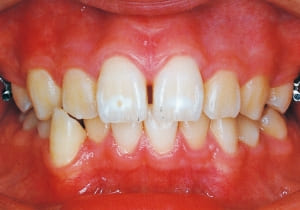

Age at initial visit : 7 y 7 m, male /Protruding upper bite. Open bite. Receding lower jaw. Protruding dual dentition.

1 Initial Visit 2-11-’88

3 Initial Visit 2-11-’88

4 Initial Visit 2-11-’88

The Class II condition is pronounced, with a significant overjet of 12.5 mm(3). Although the teeth size are large, crowding is relatively mild. The maxillofacial structure has good depth and a robust bone framework(5). The mandible itself is solid , robust gonial angle, but there is significant anterior-posterior displacement relative to the maxilla(ANB 10.0°). While there is no confirmed history of thumb-sucking or similar habits, the lower lip is already pushing up against the maxillary incisors. The cause of this condition is unknown.